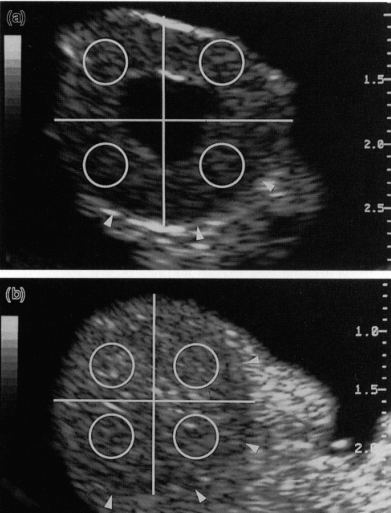

上图中具有中心腔 (a) 或无腔 (b) 的牛黄体的图像分析技术。黄体与间质由箭头划分。每个黄体的图像被分成四个相等的象限。通过放置一个覆盖每个象限大约 20% 的测量点(圆圈)来测量像素值。像素值是落在测量点下的所有像素的灰度值的平均值。超声图像上的刻度以厘米为单位。